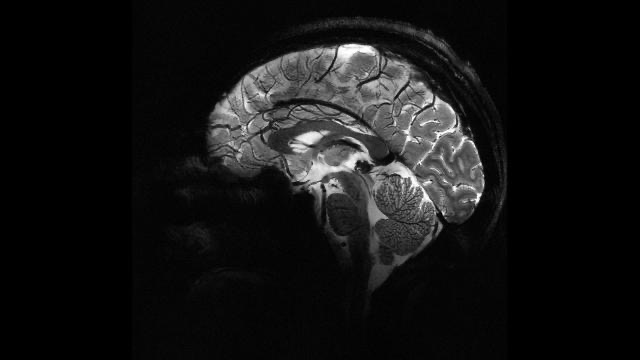

Süni intellekt epilepsiyalı uşaqlarda gizli beyin zədələrini aşkarlayır